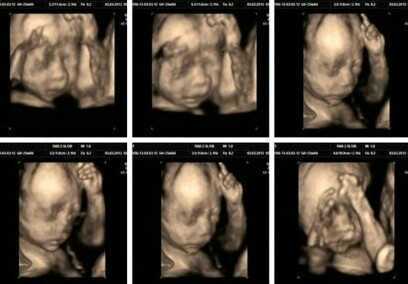

四维彩超能直观、立体显示人体器官的三维结构及动态、实时地观察立体结构,而以往的二维成像技术只能显示人体器官的某一切面。在妇产科方面,四维彩超能够对胎儿进行超声检查能立体显示胎儿的颜色、面、各器 官的发育情况,甚至胎儿在母体里的状态也可以观察到;对胎儿畸形,如唇裂、腭裂、骨骼发育异常、心血管畸形等能早期诊断。

四、四维彩超技术将宝宝的样子和动作制作成照片或VCD,让宝宝拥有蕞完整的0岁相册